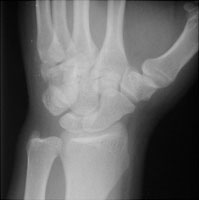

- Click on the image for a larger versionBOblique radiograph of the wrist. This shows a fracture of the body of the hamate.